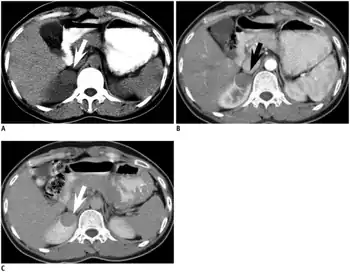

Symptoms and signs

The symptoms may be similar to those classically associated with renal cell carcinoma, and may include polycythemia, abdominal pain, hematuria and a palpable mass. Mean age at onset is around 40 years with a range of 5 to 83 years and the mean size of the tumour is 5.5 cm with a range 0.3 to 15 cm (1). Polycythemia is more frequent in MA than in any other type of renal tumour. Of further relevance is that this tumour is more commonly calcified than any other kidney neoplasm.[2] Surgery is curative and no other treatment is recommended. There is so far no evidence of metastases or local recurrence.